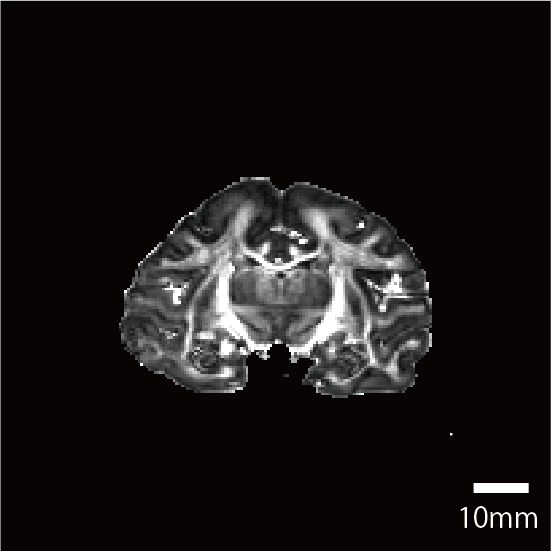

| 脳重量 | 91.9g | |

撮像情報

| T2強調画像 | 拡散テンソル画像 | |

| エコー時間 (TE) (秒) | 7.5 | 20 |

| 繰り返し時間 (RT) (秒) | 600 | 650 |

| 励起回数 (NEX) | 4 | 1 |

| 有効視野 (FOV) (mm) | 76.8, 64.4, 46 | 76.8, 64.4, 46 |

| マトリクスサイズ | 320, 256, 192 | 160, 128, 96 |

| 空間分解能 (µm) | 0.24 | 0.48 |

| b0 | - | 2 |

| 撮像時間 | 8時間 57分 | 53時間 14分 |

脳標本画像

| T2強調画像 |